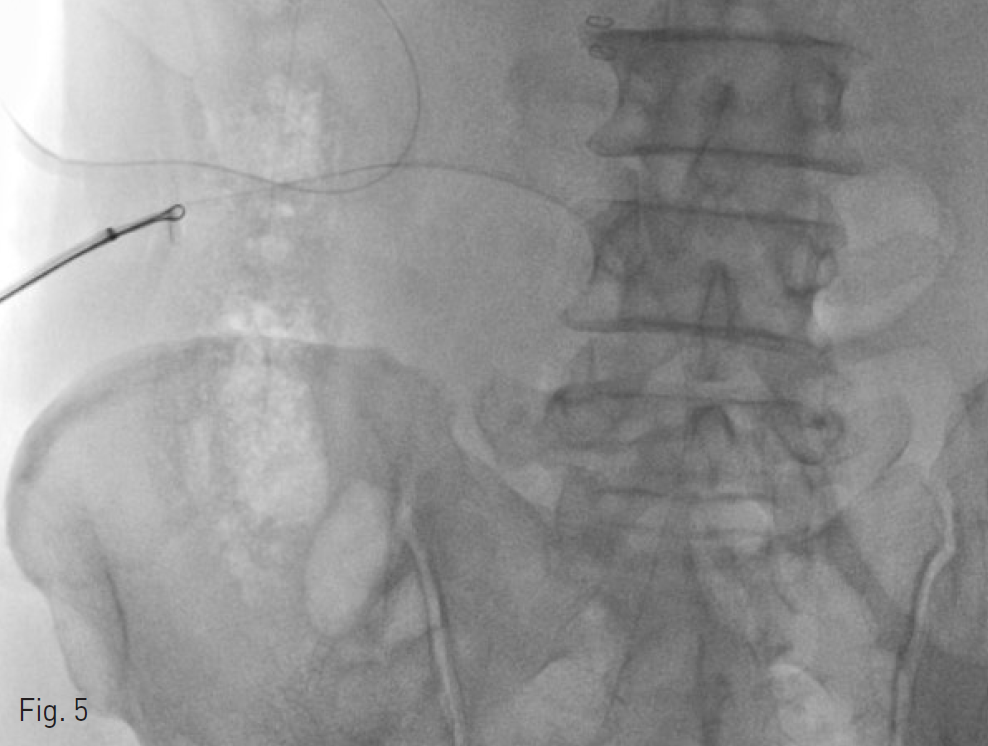

Fig. 2. Capture of the left tip of Jackson Pratt drain tube with snare.